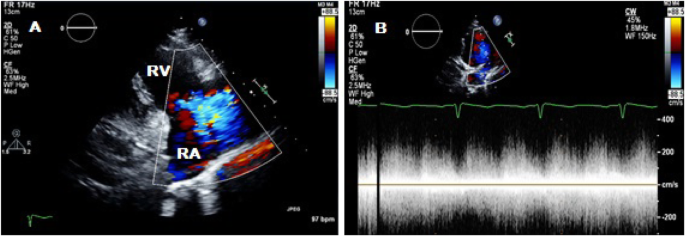

Transthoracic echocardiography (TTE) was subsequently performed for investigation of the new continuous murmur – other conditions apart from an SVA which can present with continuous murmurs include; patent ductus arteriosus, coarctation of the aorta, coronary arteriovenous fistulas and an aortopulmonary window. TTE showed normal left and right ventricular size and systolic function. To the unwary eye, the colour flow at the RV inflow view may appear like tricuspid regurgitation. However, the continuous wave Doppler clearly demonstrated a continuous wave form throughout systole and diastole (Fig. 1, Videos 1 and 2). Additionally, a significant left-to-right shunt was detected on the colour Doppler between the right coronary sinus and the right atrium (Fig. 2, Video 3). Interestingly, Doppler echocardiography detected diastolic flow reversal in the thoracic descending aorta which is more commonly seen in severe aortic regurgitation (Fig. 3).

Two-dimensional transthoracic echocardiography in parasternal long axis right ventricular inflow view; a tricuspid valve regurgitation jet on colour Doppler echocardiography. b Continuous wave Doppler through tricuspid valve regurgitation jet showing a continuous flow. RV, right ventricle; RA, right atrium